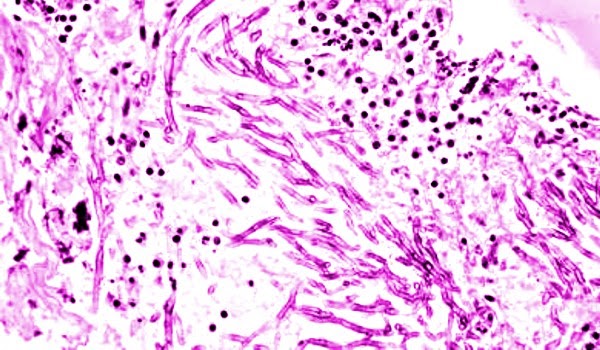

Etkeni rhabdoviruslar grubundan rna lı lyssavirus genusundan bir rhabdovirus tur.